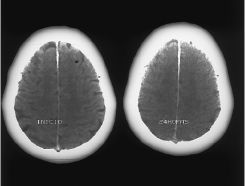

Presentamos un caso fatal de embolismo gaseoso intracraneal, provocado por el paso de aire intravenoso al territorio arterial, debido a la existencia de un foramen oval permeable y una hipertensión pulmonar asociada que favoreció el cortocircuito derecha-izquierda (embolismo paradójico). Se revisan los mecanismos fisiopatológicos de los neumoencéfalos y del embolismo paradójico, aportando una revisión bibliográfica.

We present a fatal case of intracranial air embolism produced by the passage of intravenous air to the arteries owing to the existence of a patent foramen ovale associated with pulmonary hypertension, which permitted a right-to-left shunt (paradoxical embolism). The pathophysiological mechanisms of pneumocephalus and paradoxical embolism are discussed and the pertinent literature is reviewed.